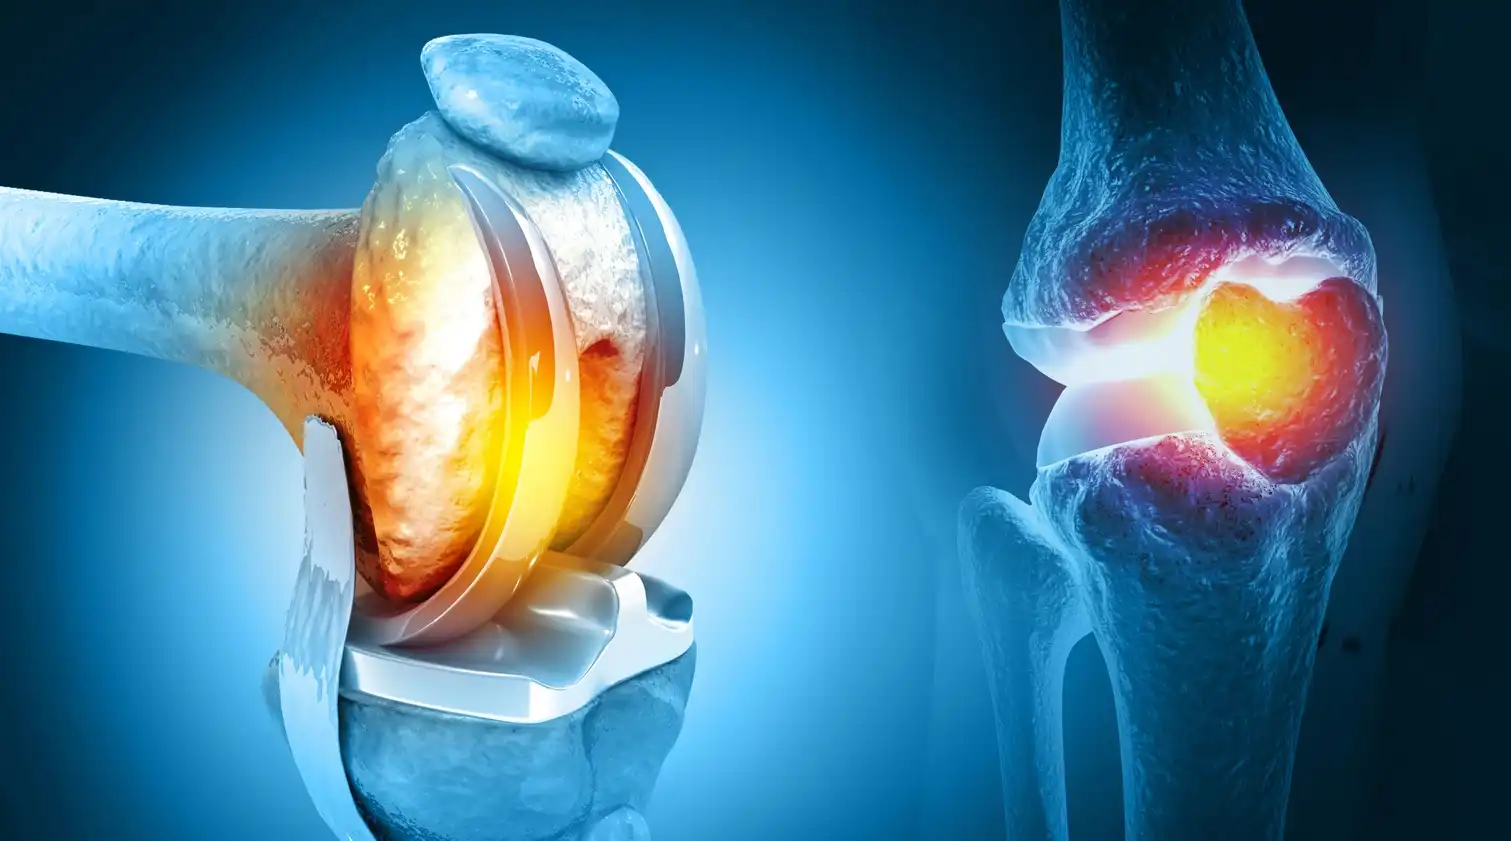

جدیدترین روش ترمیم رباط صلیبی زانو | آرتروسکوپی مدرن 1405 با کمترین درد و سریعترین بهبودی برای تمامی بیماران ادامه مطلب »